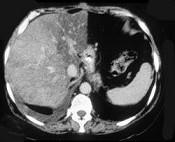

问题 男,66岁,肥胖,有糖尿病史,CT检查如图,最可能的诊断是 ( )

选项 A.局灶性脂肪肝 B.肝硬化肝癌 C.肝血管瘤 D.肝胆管细胞癌 E.肝淋巴管瘤

答案 A